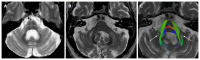

We describe common and less common diseases that can cause magnetic resonance signal abnormalities of middle cerebellar peduncles (MCP), offering a systematic approach correlating imaging findings with clinical clues and pathologic mechanisms. Myelin abnormalities, different types of edema or neurodegenerative processes, can cause areas of abnormal T2 signal, variable enhancement, and patterns of diffusivity of MCP. Pathologies such as demyelinating disorders or certain neurodegenerative entities (e.g., multiple system atrophy or fragile X-associated tremor-ataxia syndrome) appear to have predilection for MCP. Careful evaluation of concomitant imaging findings in the brain or brainstem; and focused correlation with key clinical findings such as immunosuppression for progressive multifocal leukoencephalopahty; hypertension, post-transplant status or high dose chemotherapy for posterior reversible encephalopathy; electrolyte disorders for myelinolysis or suspected toxic-drug related encephalopathy; would yield an appropriate and accurate differential diagnosis in the majority of cases.